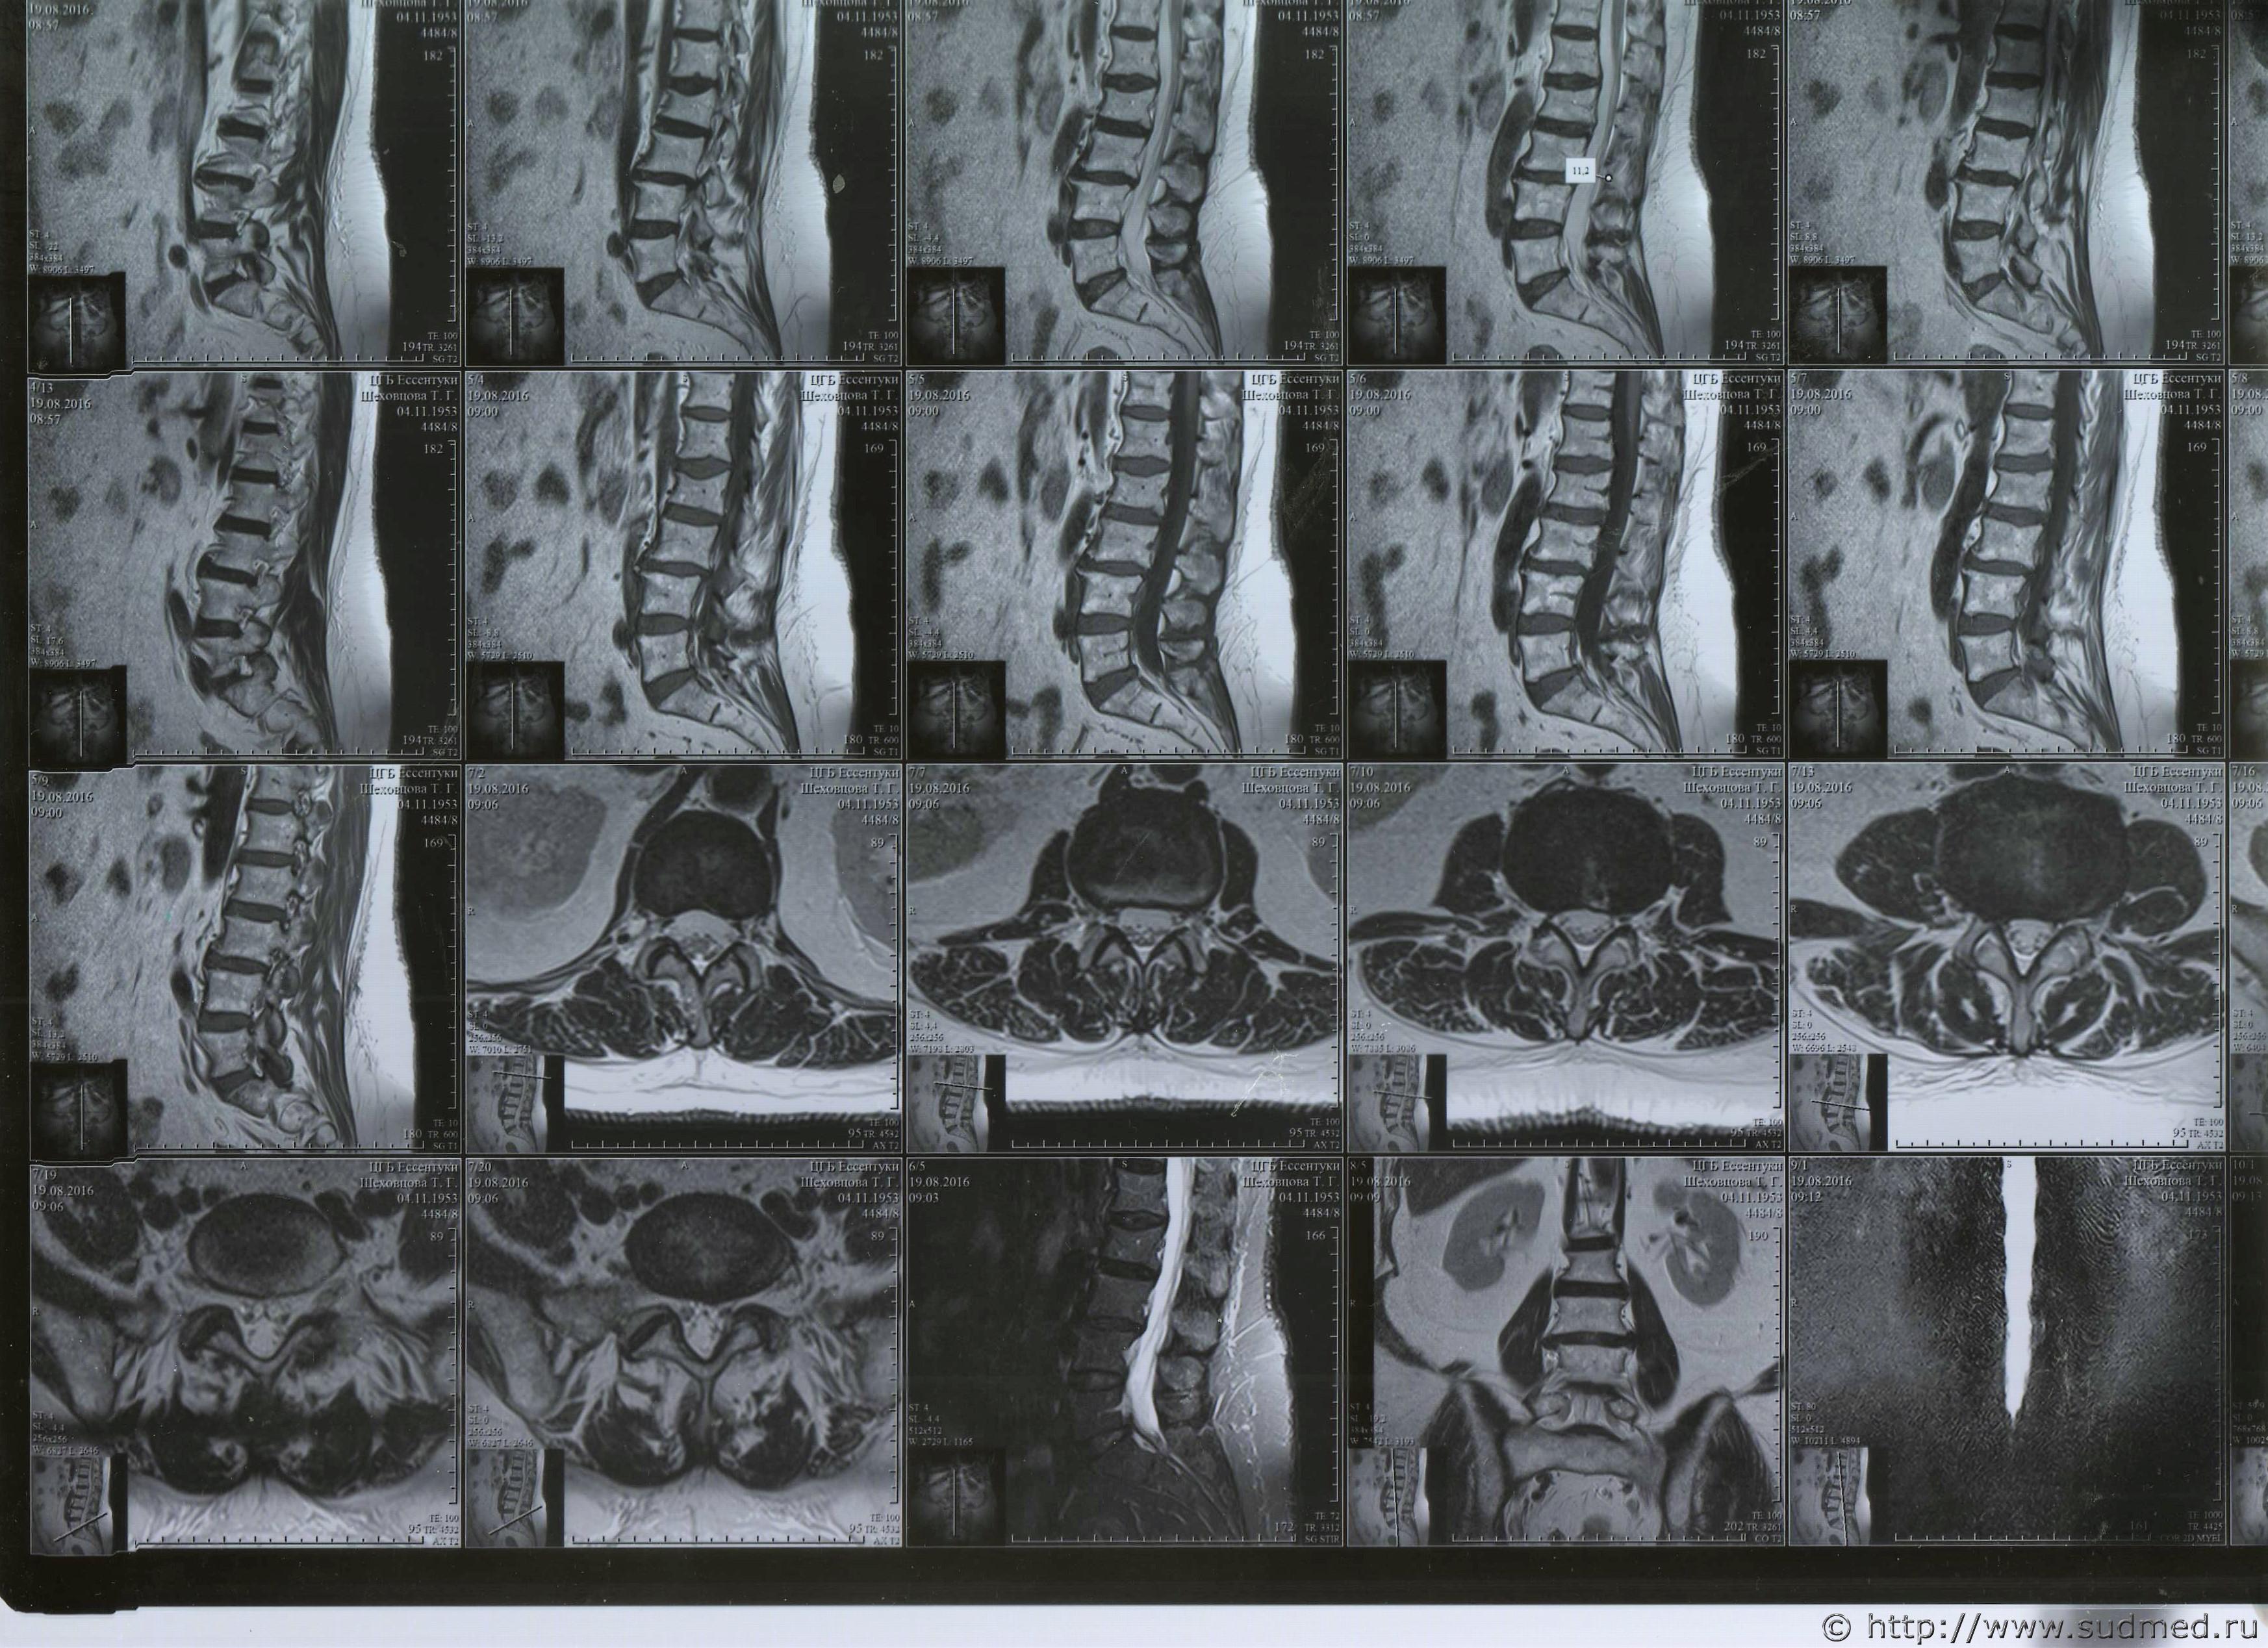

1. сделано 20.09.2015 г. заключение:

МРТ картина компрессионного перелома тела L2 позвонка.

Дегенеративно-дистрофические изменения поясничного-крестцового отдела позвоночника.Нарушения статики пояснично-крестцового отдела позвоночника. Грыжи дисков L1-S1/ Спондилоартроз. Относительный стеноз позвоночного канала.

Сигнал от костного мозга позвонков диффузно неоднородный- для детализации костных патологических изменений рекомендуется компьютерная томография.

2. Заключение КТ от 05.10.2015 г.

КТ-признаки консолидированного компрессионного перелома тела L2. Постравматического спондилоартроза, спондилеза, постравматического остеохондроза поясничного отдела позвоночника, Циркулярные, дорзальные протрузии МПД L2-L5-S1/

Дорзальная грыжа МПД L5-S-1

3/ Заключение: МРТ от 16.02.2016 г.

Консолидированный компрессионный перелом тела L2 с передней клиновидной компрессией 3 степени. МР картина остеохондроза ПОП, " ст.- в ПДСL2-L3, L4-L5, L5-S1 задние протрузии дисков сагиттальный размер которых до - 3 мм, протрузии компремируют дуральный мешок.

Уважаемые доктора, нужны ли снимки по перелому правой голени? и Заключения по МРТ и КТ.Ранее представляла результаты обследования...Сделала копию снимков по КТ и МРТ( только вот какого качества получились не знаю.)

Посмотрите, пожалуйста